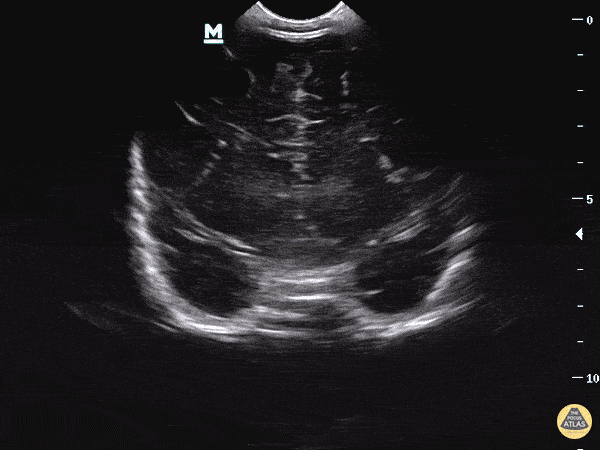

Clip 3: The coronal plane has the indicator marker to the right and is placed on the anterior fontanelle. The ultrasound beam is swept from the anterior to posterior aspect of the head.